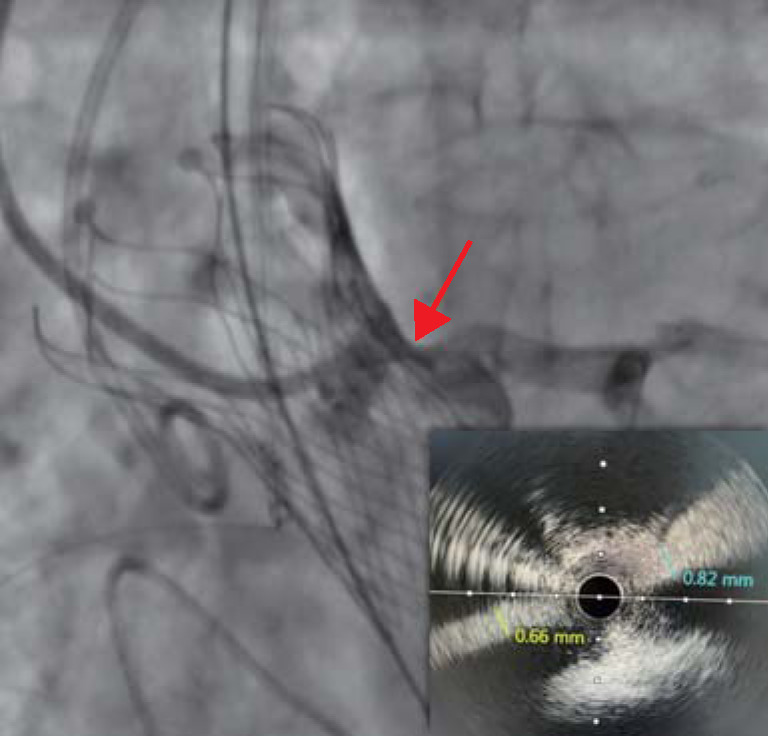

A 72-year-old patient with quadricuspid aortic valve underwent transcatheter aortic valve replacement due to severe valve stenosis accompanied by moderate insufficiency. As initially planned, the right coronary artery was protected during the procedure. However, after the artificial valve was released, the left coronary artery was found to be blocked, so a coronary protection stent was implanted in the left coronary artery ostium under the guidance of intravascular ultrasonography. This case indicates that for patients with a quadricuspid aortic valve undergoing transcatheter aortic valve replacement, in addition to preoperative measurement of the aortic root, attention should also be paid to the coronary artery obstruction caused by the displacement of the artificial valve frame during the procedure.